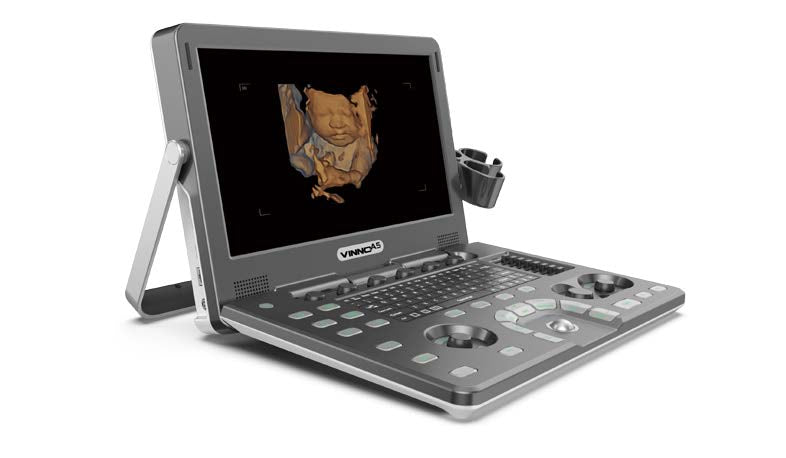

A5 Vinno Portable Ultrasound Colour Doppler

A5 Vinno Portable Ultrasound Colour Doppler

Features:

- Responsive touchscreen,

- streamlined workflow and customizable,

- user-defined portables to maximize workflow efficiency

- Ultra-sensitive touchscreen for easy operation

- One-click auto-optimization

Specifications:

- 15 inch high resolution monitor

- 8 inch touch screen